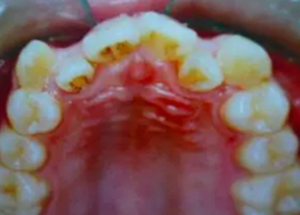

3.png

一般來說,拔牙以后的牙縫可以被兩個方面的牙齒移動所關(guān)閉,一個是前面不齊、前突的牙齒向拔牙間隙移動,占據(jù)部分拔牙間隙,還有就是后面的大牙也可以向關(guān)(拔牙間隙)移動,這樣就可以關(guān)閉了這個間隙。

對于兒童和成年人矯治,其實,牙齒的移動相理都是一樣的,所以孩子、成人矯治都可以拔牙。他們的不同之處在于:兒童處于生長發(fā)育的旺盛期,牙齒對各種矯治力的反應(yīng)比較好,牙齒移動也相對快些。而成人,生長發(fā)育已經(jīng)停滯,牙齒移動需要重新調(diào)動機體的反應(yīng),牙齒移動就會相對慢些,矯治的療程也會長一點。還有就是成人牙移動后,同樣需要相對長的時間牙齒才能在新的位置上穩(wěn)定下來。